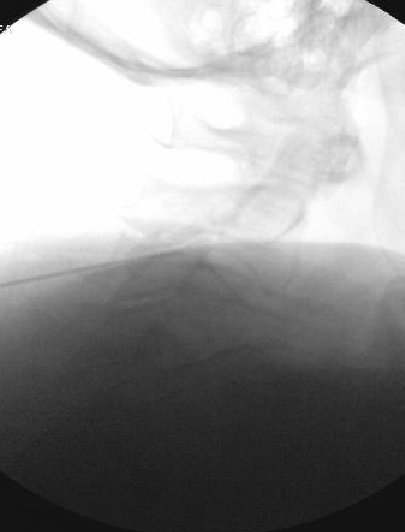

Only thing I do differently is aim for a touch more posterior placement of the needle. I try to make sure the very tip of the needle is at but not beyond the x in the image below. I also take a final lateral right before RFA. I think it helps reduce the frequency of neuritis to be a bit more posterior.

View attachment 395708

I appreciate the input, but I'm using a 10mm active tip and I'm burning quite a bit of MBN in that pic right there. Going more posterior theoretically means I'm getting less of it.

Based on some discussion on here a few years back, I tried burning 1/2 way along the pillar rather than anterior edge, but felt like I saw an immediate increase in neuritis. I suspect there are at least 2 different causes. Some neuritis comes from burning nerves with a sensory input to the skin, unavoidable, but some comes from being a little off target and only irritating rather than completely burning a medial branch nerve.